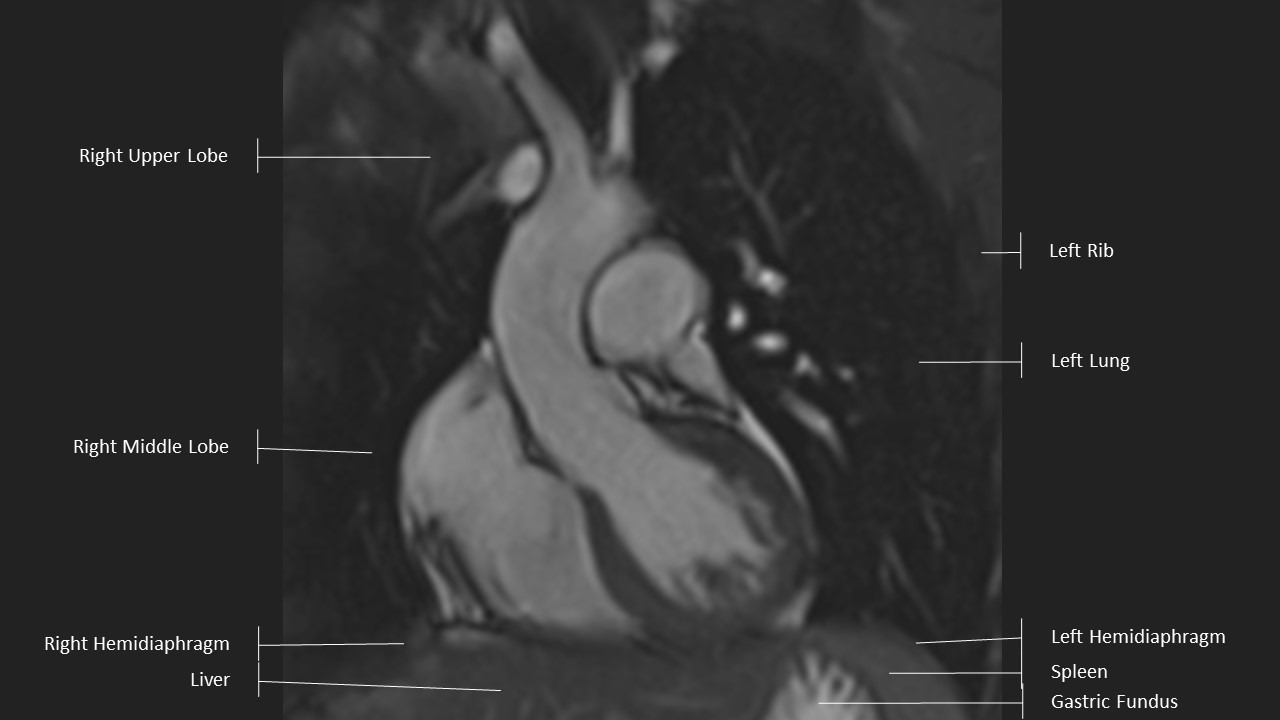

Left Ventricular Outflow Tract (LVOT) View

LVOT View